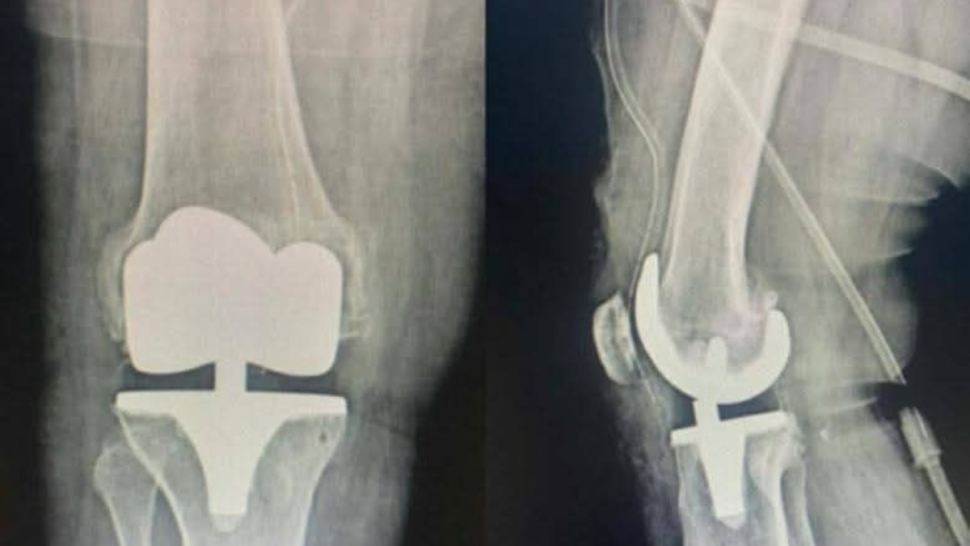

جندوبة: نجاح عملية تركيب مفصل اصطناعي كامل للركبة بالمستشفى الجهوي

وتُعدّ هذه العملية وفق بلاغ صادر عن الادارة الجهوية للصحة بجندوبة، من العمليات الدقيقة في جراحة العظام بالتنسيق مع قسم التخدير والإنعاش، وقد تكلّلت بالنجاح، في خطوة مهمّة تعيد هذا النوع من التدخلات الجراحية إلى المستشفى بعد سنوات.

ويمثل هذا الإنجاز إضافة نوعية للخدمات الجراحية بالمستشفى الجهوي بجندوبة، ويعكس كفاءة الإطارات الطبية وحرصها على تطوير الرعاية الصحية لفائدة المرضى بالجهة وفق البلاغ.